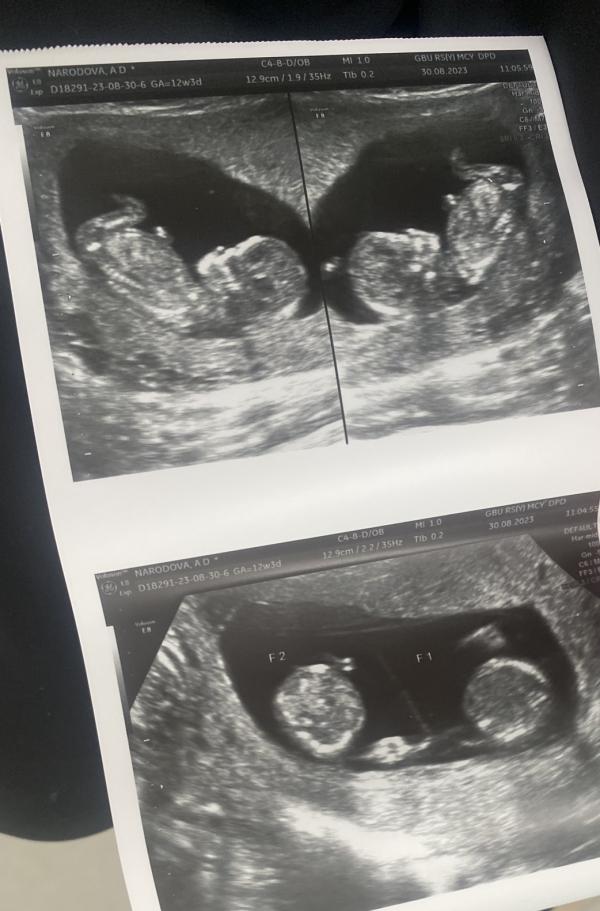

Дихориальная диамниотическая двойня - у каждого плода своя плацента и амниотическая полость.

Монохориальная диамниотическая двойня - плацента общая для обоих плодов, две амниотические полости.

Монохориальная моноамниотическая двойня - у плодов общие плацента и амниотическая полость.